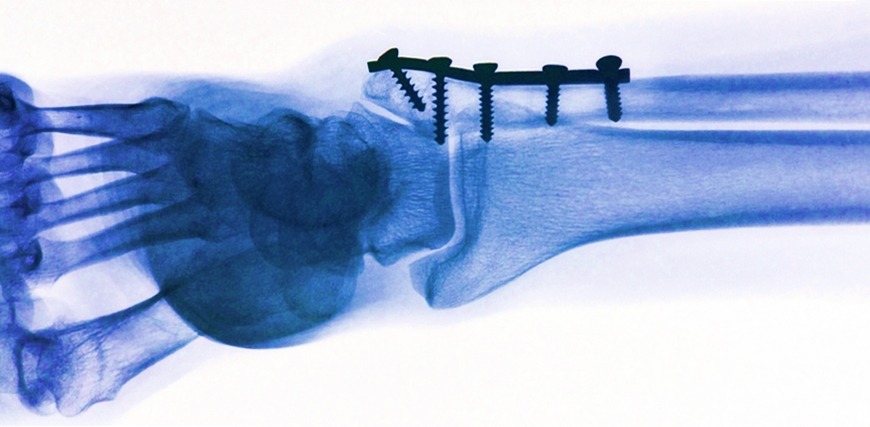

Então, quando os ortopedistas querem consertar ósseos quebrados eles usam pinos e placas de titânio (Ti) ou aço. Bom, esses materiais são mecanicamente e quimicamente muito estáveis no corpo. Mas depois de um tempo eles precisam ser removidos. Dessa forma, a recuperação dos ossos baseia-se em duas cirurgias. Ou seja, uma para colocar o pino ou a placa e outra para retirá-los.

Uma alternativa para reduzir uma das cirurgias é utilizar de materiais orgânicos que se dissolvem com o tempo. Mas, esses materiais orgânicos têm algumas desvantagens, como falta de resistência mecânica ou produtos de degradação desfavoráveis. Dessa forma, pesquisadores do Instituto de pesquisa Suíço EMPA (Materials Sciences and Technology) estão trabalhando para resolver esse problema. Eles estão desenvolvendo materiais para resolver problemas de fraturas com o alcalino terroso magnésio (Mg).

A grande vantagem desses materiais é que ele são mecanicamente robustos e se dissolvem no corpo. Segundo, os pesquisadores do EMPA os materiais de magnésio são particularmente interessantes para aplicações ortopédicas médicas em crianças cujos ossos estão crescendo rapidamente.

Então, nos pequeninos os materiais de magnésio não prejudicam o crescimento ósseo e livram os pequeninos de uma segunda cirurgia. Além disso, os riscos de infecção podem ser minimizados e os custos podem ser reduzidos consideravelmente. Portanto, agora você não precisa tirar mais o pino do osso